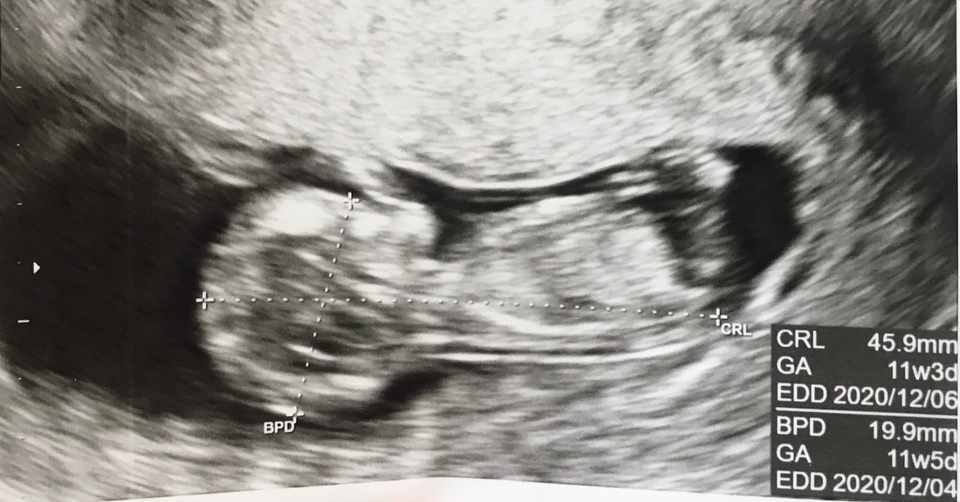

妊娠12週目 12w0d 6d のエコー写真とエピソード 妊娠4ヶ月 Cozre コズレ 子育てマガジン